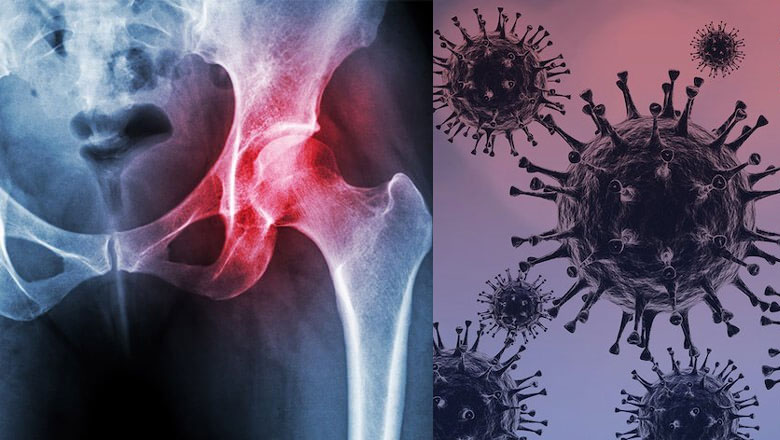

അവാസ്‌കുലര്‍ നെക്രോസിസ് ! ബ്ലാക് ഫംഗസിനു ശേഷം കോവിഡ് മുക്തരെ തേടി മറ്റൊരു രോഗം കൂടി; അതീവ മാരകമായ ഈ രോഗത്തെക്കുറിച്ചുള്ള വിവരങ്ങള്‍ ഇങ്ങനെ…

ഇതിന് പിന്നാലെയാണ് ആഴ്ചകള്‍ക്ക് ഇപ്പുറം മറ്റൊരു ഗുരുതരരോഗം കോവിഡ് വന്നവര്‍ക്കിടയില്‍ റിപ്പോര്‍ട്ട് ചെയ്യുന്നത്. അവാസ്‌കുലര്‍ നെക്രോസിസ് എന്ന അസ്ഥികോശങ്ങള്‍ നശിക്കുന്ന രോഗാവസ്ഥയാണ് മൂന്ന് രോഗികളില്‍ കണ്ടെത്തിയത്.

തുടക്കത്തില്‍ തന്നെ രോഗനിര്‍ണയം നടത്തിയാല്‍ എളുപ്പം അസുഖം ഭേദമാക്കാന്‍ സാധിക്കും. അങ്ങനെയങ്കില്‍ ശസ്ത്രക്രിയ ഒഴിവാക്കാം. അസ്ഥികളിലേക്ക് താത്കാലികമായോ പൂര്‍ണമായോ രക്തയോട്ടം നിലയ്ക്കുന്നതാണ് അവസ്ഥ.

അസ്ഥികോശങ്ങള്‍ നശിക്കുന്നതോടെ അസ്ഥികളുടെ പ്രവര്‍ത്തനം നിലയ്ക്കാം. സന്ധികളെയും ഇത് ബാധിക്കാം.സന്ധിവേദനയാണ് ഇതിന്റെ മുഖ്യലക്ഷണം.

സ്റ്റിറോയിഡുകളുടെ ദീര്‍ഘകാലമായ ഉപയോഗത്തിന് പുറമേ പരിക്ക്, പൊട്ടല്‍, രക്തക്കുഴലുകള്‍ക്ക് തകരാര്‍ സംഭവിക്കല്‍ എന്നി കാരണങ്ങള്‍ കൊണ്ടും അവാസ്‌കുലര്‍ നെക്രോസിസ് സംഭവിക്കാമെന്ന് ഡോക്ടര്‍മാര്‍ പറയുന്നു.